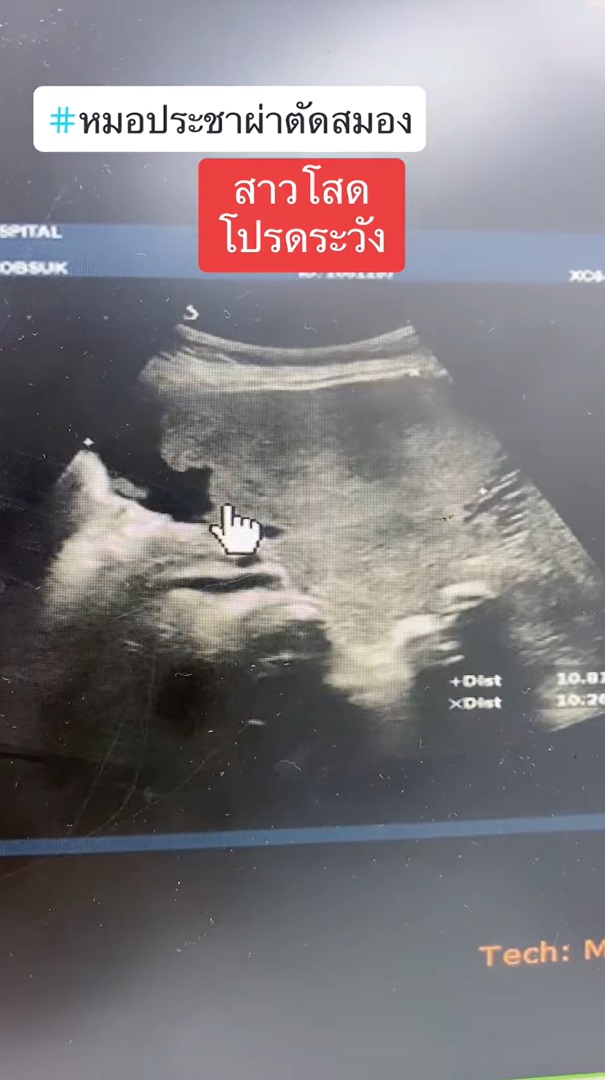

ทำเอาเหล่าสาวโสดถึงกับร้อน ๆ หนาว ๆ หลังจากที่ นายแพทย์ประชา กัญญาประสิทธิ์ หมอผ่าตัดสมอง ออกมาโพสต์เตือนภัยใกล้ตัวที่มีแนวโน้มจะเกิดกับสาวโสดได้ง่ายกว่าคนที่มีลูก โดยได้ยกเคสผ่าตัดเคสหนึ่งมาเป็นกรณีศึกษา ระบุว่า มีผู้ป่วยหญิง อายุ 57 ปี เป็นสาวโสดอยู่คนเดียว มาหาหมอด้วยอาการพูดจาสับสน ซึ่งผลการตรวจเอกซเรย์ พบว่า มีสมองตายหลายจุด ตายทั้งข้างหน้า ข้างหลัง ลามไปจนถึงท้ายทอย ทำให้ตามัว และมีจุดเลือดออกในหย่อมที่สมองตายด้วย และยังตรวจพบอีกหลายอย่าง อาทิ

โดยเคสนี้มาตรวจเนื่องจากญาติร้อนใจ หาสาเหตุไม่ได้ว่าทำไมสมองตายมากขนาดนี้ ก่อนจะเจอแจ็กพอตว่ามีก้อนเลือดเบ้อเริ่มอยู่ในอุ้งเชิงกราน ซึ่งอายุ 57 ปี ไม่ใช่การตั้งครรภ์อย่างแน่นอน พอเอาชิ้นเนื้อไปตรวจพบว่าเป็นมะเร็งรังไข่แล้วทำให้เกิดภาวะลิ่มเลือดไปอุดเส้นเลือดที่อวัยวะต่าง ๆ ของร่างกาย